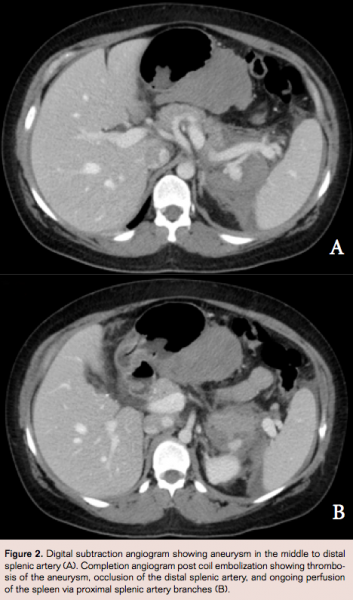

Under conscious sedation and using local anesthetic, arterial access was gained via the right common femoral artery using a 4 French sheath and Cobra C2 catheter (Cook Medical). Coil embolization of the aneurysm sac as well as the proximal and distal splenic artery was performed using Nester embolization coils (Cook Medical). Completion angiogram showed thrombosis of the aneurysm, occlusion of the distal splenic artery, and ongoing perfusion of the upper pole of the spleen via proximal splenic artery branches (Figures 2A and 2B). Postoperatively the hemoglobin was 76g/L and the patient was started on darbepoetin, iron, folic acid and B12 supplementation. A CT scan performed on day 1 post embolization showed no evidence of ongoing aneurysm leak, splenic infarction or pancreatitis. The patient was discharged well on day 2 and has elected not to attend postoperative follow-up due to her distance from the treating facility.